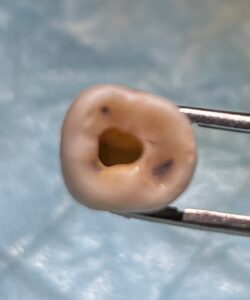

N先生

N先生は本セミナーに来るまでNi-Ti Rotary Fileなど触れたこともなかったという。

しかし、ここまできちんと形成・根充できる。

この先生も合格だ。

今後は自費で診療しましょう。